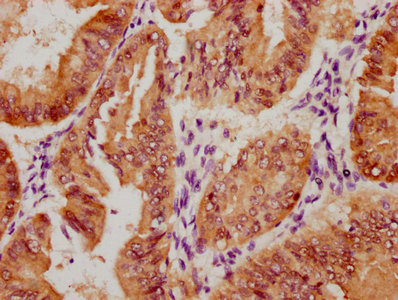

Immunohistochemistry of paraffin-embedded human liver cancer using CSB-PA026121LA01HU at dilution of 1:100